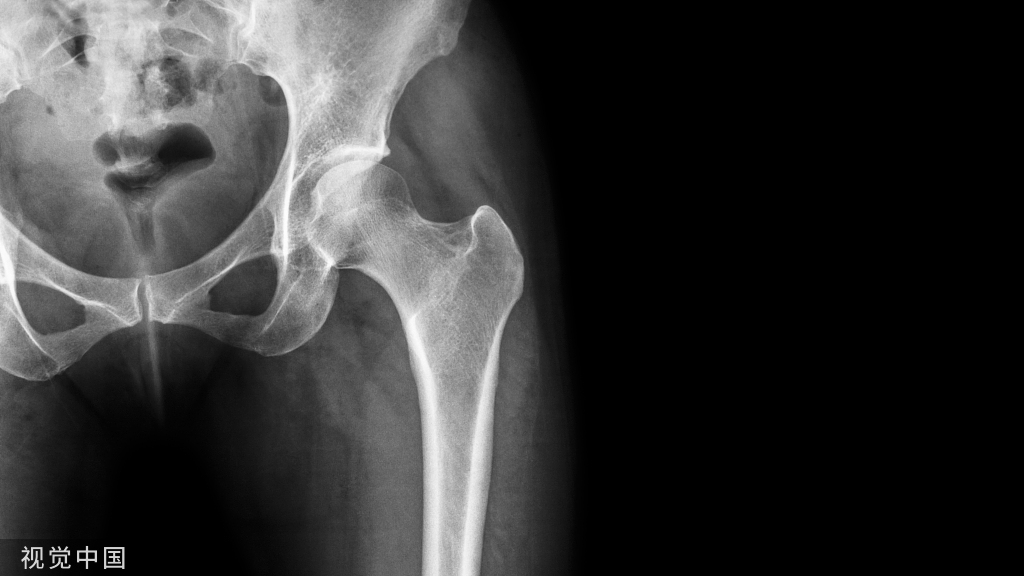

74岁男性,以间歇性跛行和左下肢坐骨神经痛1月为主诉就诊。查体未见皮肤病变,无肌力下降,无感觉障碍,无直肠膀胱障碍。MR提示L4/5椎管狭窄,如下图。

口服非甾体类抗炎药无效,2周内对其进行2次硬膜外封闭,效果欠佳,此时患者抱怨足面和足底水泡、破溃和红斑,且患者休息时疼痛症状无缓解。咨询皮肤科医生,诊断坐骨神经带状疱疹。给予抗病毒治疗1周后症状缓解。